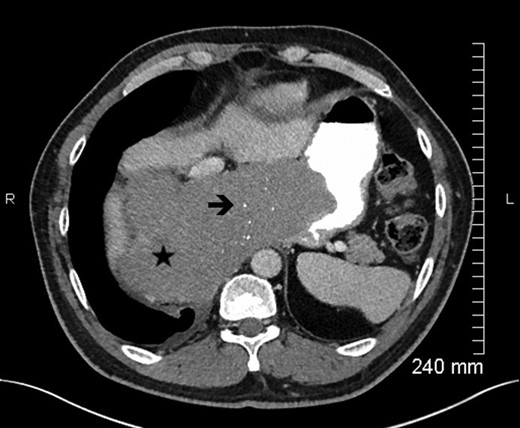

Blood test revealed elevated inflammatory markers (white cell count 21.49 g/L, C reactive protein 359 mg/L, Fibrinogen 7.4 g/L). An abdominal CT-scan showed a recurrence of digestive tumor in pelvis with a digestive presacral fistulization without circumscribed fluid collection. A sagittal section abdominal CT and magnetic resonance imaging (MRI) (Figs. 1–2) showed colic fistula to the presacral collection measured to 38.8 × 9.54 mm with infiltration of adjacent soft tissue and which continues to the spinal canal through the sacral S1 left hole with multiple epidural abscess from L4 to S4. There was osteitis of the sacrum and arachnoiditis.

Axial view contrast-enhanced MDCT (portal phase) with oral opacification, in a x year-old men with a large esophageal GIST, showing a lesion (★), well-circumscribed, with small calcifications (è) (rare). The lesion is homogeneous (no kystic or necrotic parts) without hypervascularization.